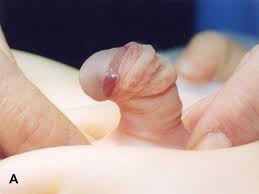

Phimosis

Phimosis is normal in small babies and in toddlers. But in older children it may be the result of a skin condition that has caused scarring. It is not usually a problem unless it causes any symptoms. Immediate treatment is needed in cases where phimosis causes problems like difficulty in urinating.